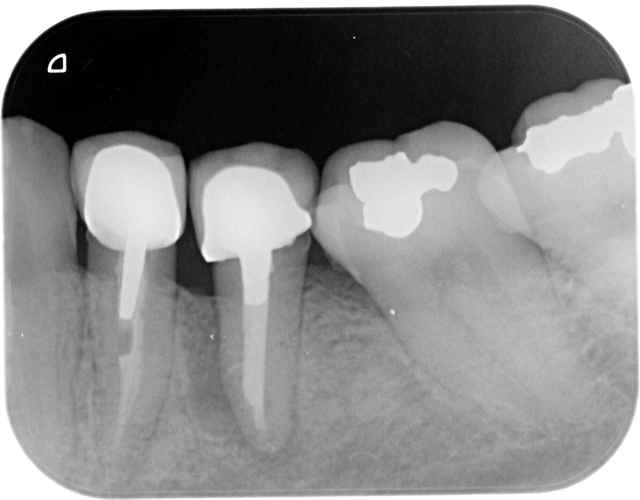

Plus sérieusement sur le premier cas le foret en place est le terminal de 12x3,5, je le trouve pas si mal l'axe 3d, mais j'ai un peu forcé sur le biomat

pour l'autre cas, je suis aussi dans l'axe,j'avais décalé le deuxieme forage en palatin pour faire une expansion

vesti, puis j'ai choisi la facilité

pxav c'est pour toi , tu te souviens

50 minutes, 3implants et 3 hemos

En 33 c'est un bouchon, j'ai tapé la corticale interne et l'artériole en meme temps et l'ai pas réussi à la traversée(l'artériole)

çà c'est un vrai probleme de 3D , vous m'avez porté la poisse

Suis moins patient que pxav, c'est un 8x3,7 je pense que çà va aller qd meme

Olivier et les autres, pouvez-vous détailler ce qui dans le positionnement 3D a amené un tel échec esthétique?

Je dirai un axe vestibulo-palatin trop incliné en vestibulaire, mais est-ce la seule cause?

>Je dirai un axe vestibulo-palatin trop incliné en vestibulaire, mais est-ce la seule cause?<